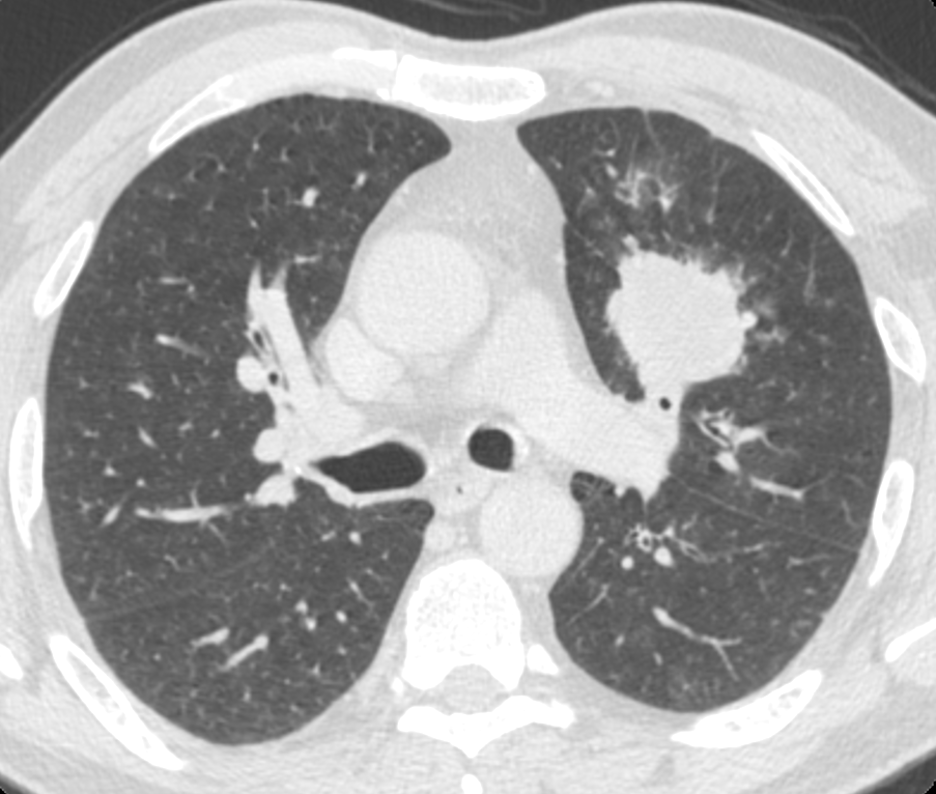

UVA Health Cancer Center is joining more than 50 other top cancer organizations in calling to increase access to and use of low-dose computed tomography (CT) scans for Americans at high risk for lung cancer.

The U.S. Preventive Services Task Force recommends annual screening for people ages 50-80 who have smoked at least a pack a day for 20 years (or an equivalent). However, only 5.7% of eligible Americans were screened for lung cancer before the COVID-19 pandemic — while screening rates for breast, cervical and colon cancers ranged between 60% and 80%. In addition, screening rates have decreased for all cancers because of the pandemic.